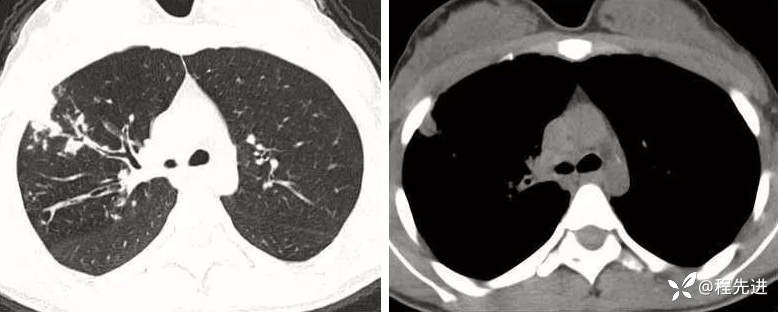

病例二:

看图说话